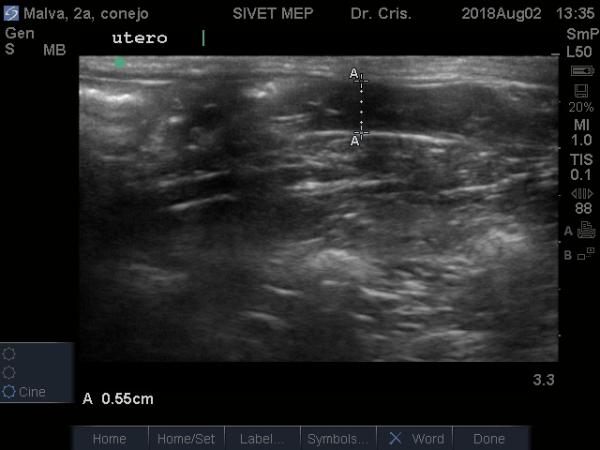

Me podrían ayudar a verificar si hay algo extraño en el estomago de mi conejita?